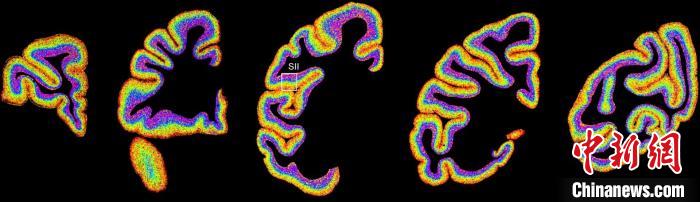

圖為不同類型細(xì)胞在獼猴大腦上的分布切片。 中國(guó)科學(xué)院腦科學(xué)與智能技術(shù)卓越創(chuàng)新中心 供圖

李澄宇說,科研人員做的事情好似“查戶口”,也就是搞明白猴腦里有哪些細(xì)胞、這些細(xì)胞在哪些位置。搞明白這些就形成了一個(gè)大的數(shù)據(jù)集,科研團(tuán)隊(duì)挖掘這個(gè)數(shù)據(jù)集,發(fā)現(xiàn)了很多有意思的現(xiàn)象:比如,興奮性神經(jīng)元、抑制性神經(jīng)元以及非神經(jīng)元在大腦皮層中的分布呈現(xiàn)明顯的特異性,也就是不同細(xì)胞“住”哪,有一定規(guī)律。